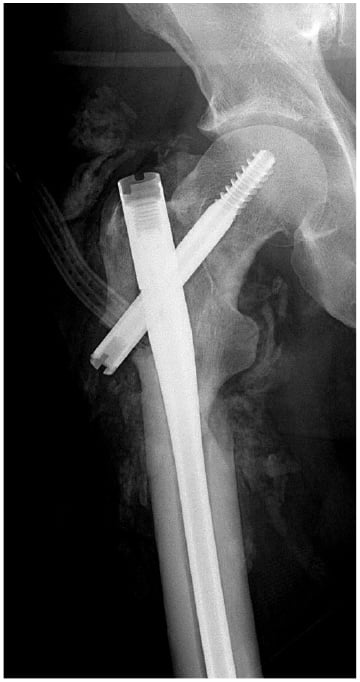

A 62-year-old man sustained a ground-level fall resulting in a right intertrochanteric femur fracture in June 2020. He was overweight (body mass index of 26.55) and his prior medical history included asthma requiring intubation, hypertension, type 2 diabetes, vertebral osteomyelitis/epidural abscess, and pulmonary embolus. He underwent operative fixation at another hospital shortly after injury (Fig. 1). His postoperative course was complicated by infection requiring operative debridement 2 months later. On postoperative day 1, against medical advice, the patient sought evaluation at another hospital. He was ultimately discharged from that hospital and had follow-up with the primary surgeon.

Figure 1: Plain X-ray of the right hip, the first taken after initial debridement.